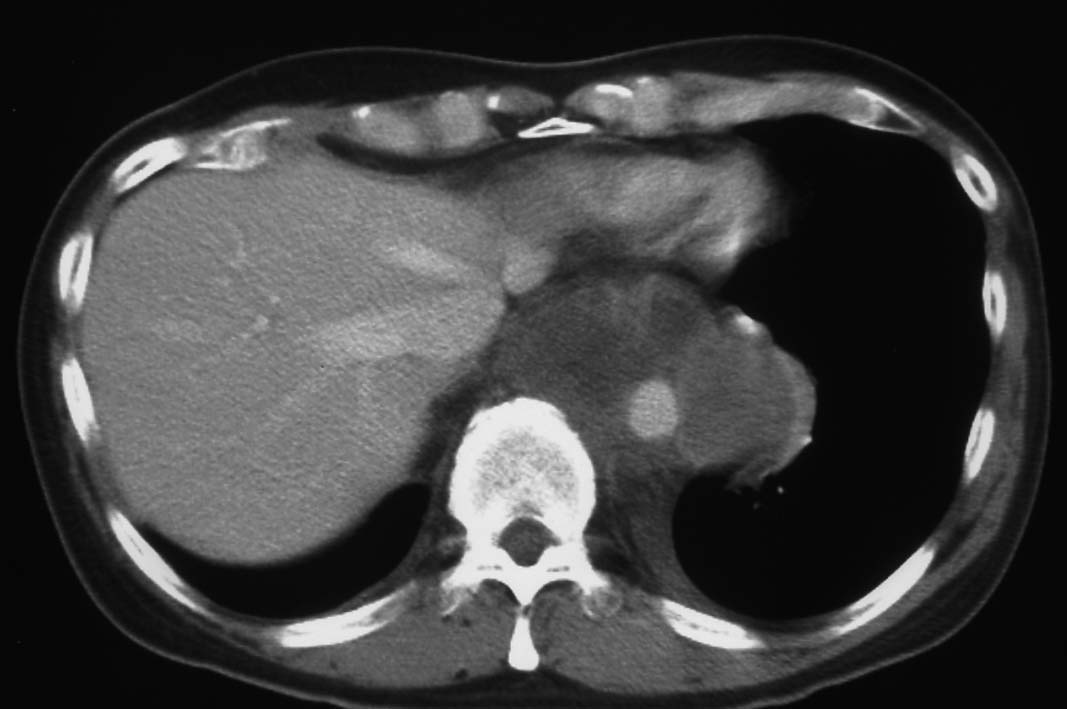

胸腔鏡下ブラ切除術5ヵ月後, 縦隔腫瘤で再発. 他院で腫瘍切除+右肺上葉切除を施行. 肉眼的には腫瘍は完全に切除できた.

初診から11ヵ月, 胸部つかえ感出現. CTで気管分岐部から横隔膜食道裂孔を通り, 腹腔内へ進展, 食道および大動脈を囲繞する巨大な腫瘍が再発した. 他院での抗がん剤感受性テストの結果より, CDDP+5FUによる化学療法がおこなわれたが効果乏しく全身状態悪化. 呼吸不全が進行し初診より約1年の経過で永眠された.